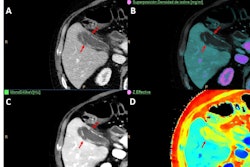

In some settings, spectral CT was only employed for very specific applications, such as cardiac imaging or oncology, while other departments relied entirely on conventional single-energy CT. Several respondents noted that while spectral CT provides extra data (such as perfusion maps or virtual noncontrast images), the information is not always considered clinically useful or relevant, leading to limited utilization, Tsapaki and colleagues noted.

Despite the challenges, the most common spectral CT clinical applications appear to be pulmonary embolism, especially in older patients or those requiring reduced contrast due to renal impairment, the survey highlighted. Abdominal imaging was frequently mentioned, often for lesion characterization, perfusion analysis, or low-contrast-dose studies.

Several sites also reported cardiac or oncologic imaging, musculoskeletal assessments, and routine radiation therapy planning, particularly for head, neck, prostate, and spine. Moreover, some sites are using spectral CT for stroke assessment and postoperative brain scans, as well as differentiating hemorrhage from contrast, according to the findings.